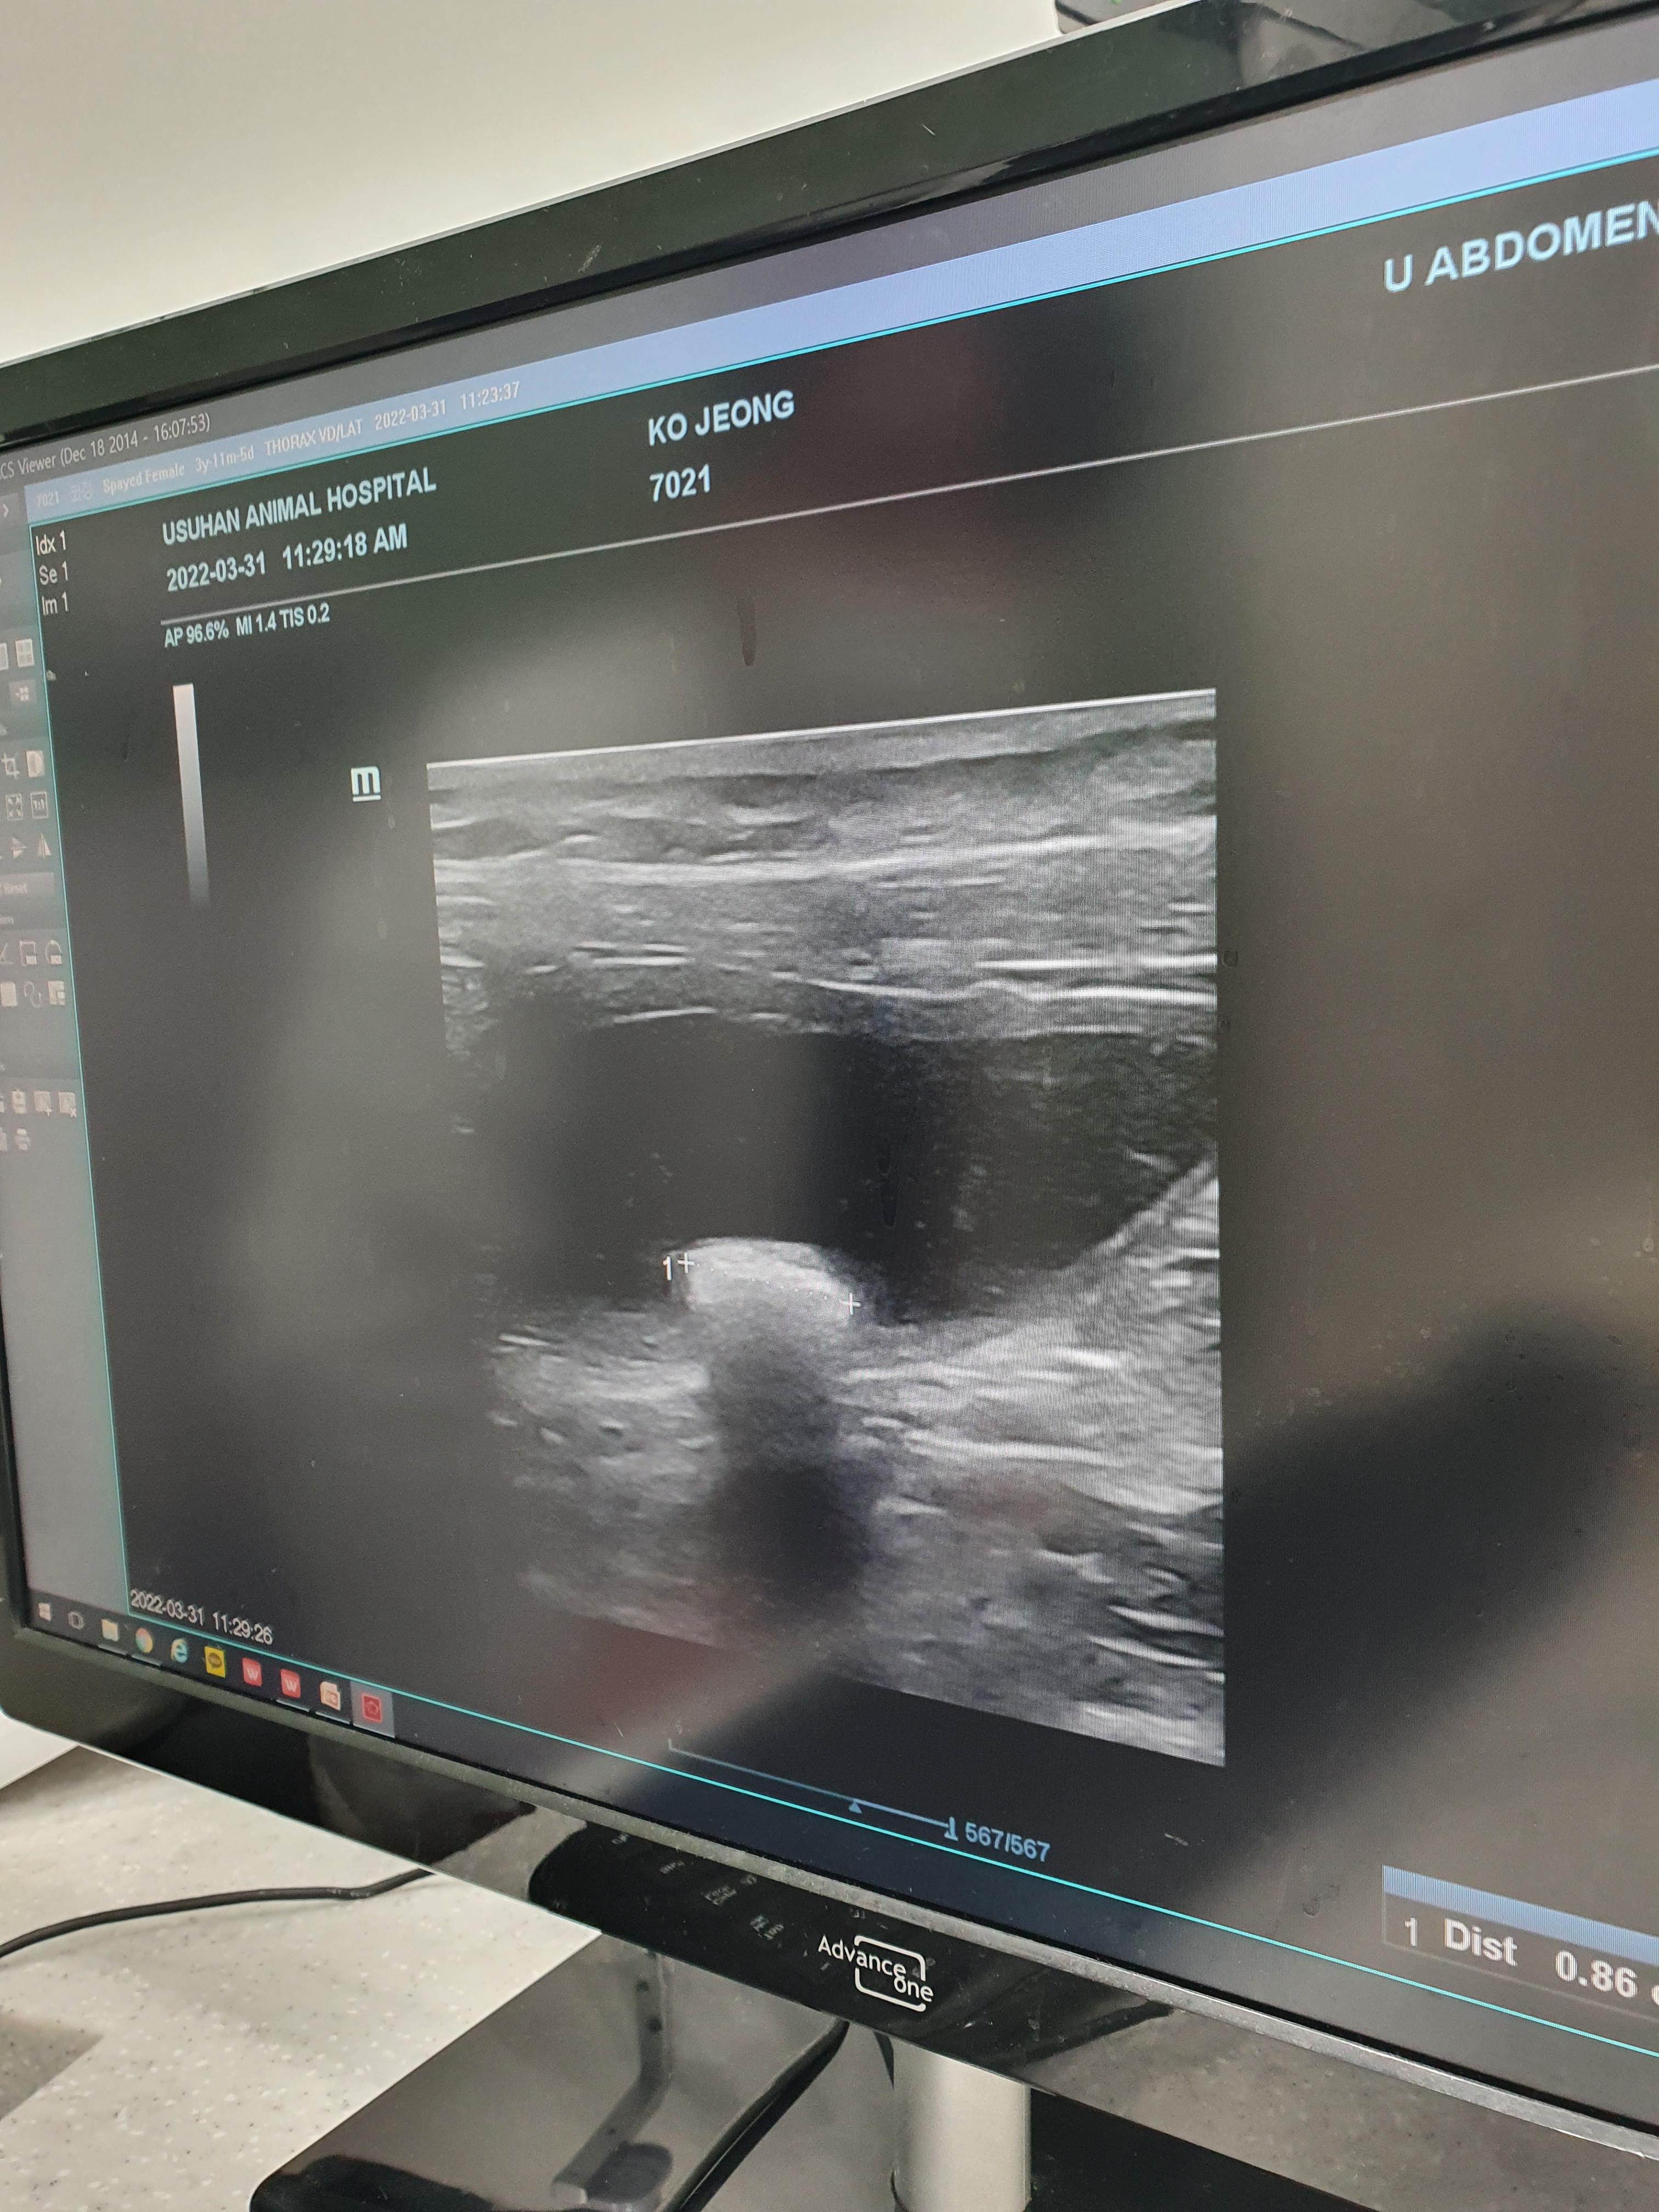

안고 들어가서 방광초음파와 엑스레이를 찍고 나왔다.

초음파에 약 0.9mm 사이즈의

결석이 발견됐다고 하셨다.

거의 1cm가 되는 결석이라니

엑스레이상으로도 너무 또렷이 보였다.